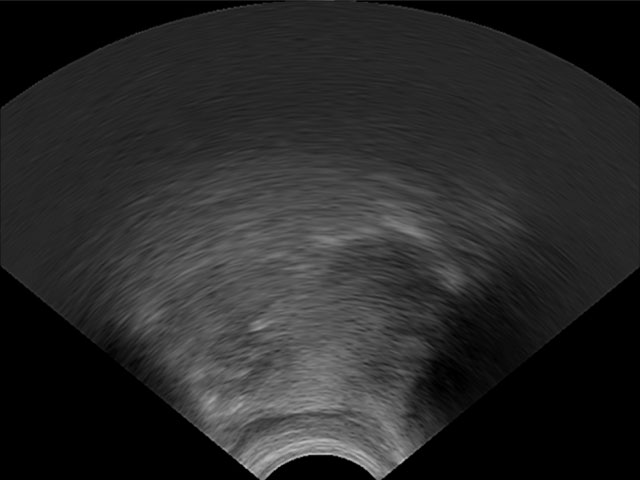

LinguaSound 3D, which is language independent, can simplify the interpretation of conventional ultrasound tongue imaging. A comparison of both imaging techniques is illustrated below for a normal English speaker:

| Conventional ultrasound tongue imaging | LinguaSound 3D | |

|---|---|---|

| High-Front Vowel /i/ | ![]() |

![]() |